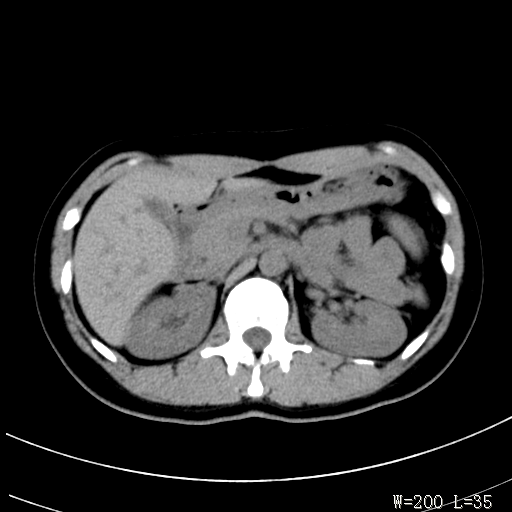

标题: CT25345:右肾占位。 [打印本页]

标题: CT25345:右肾占位。

女,30岁,右腰部胀痛3个月。

增强无明显强化,先考虑血管平滑肌脂肪瘤,建议作薄层扫描右mri检查,

感觉像囊肿.

囊肿!

考虑右肾近上极囊肿;建议必时行mri检查。